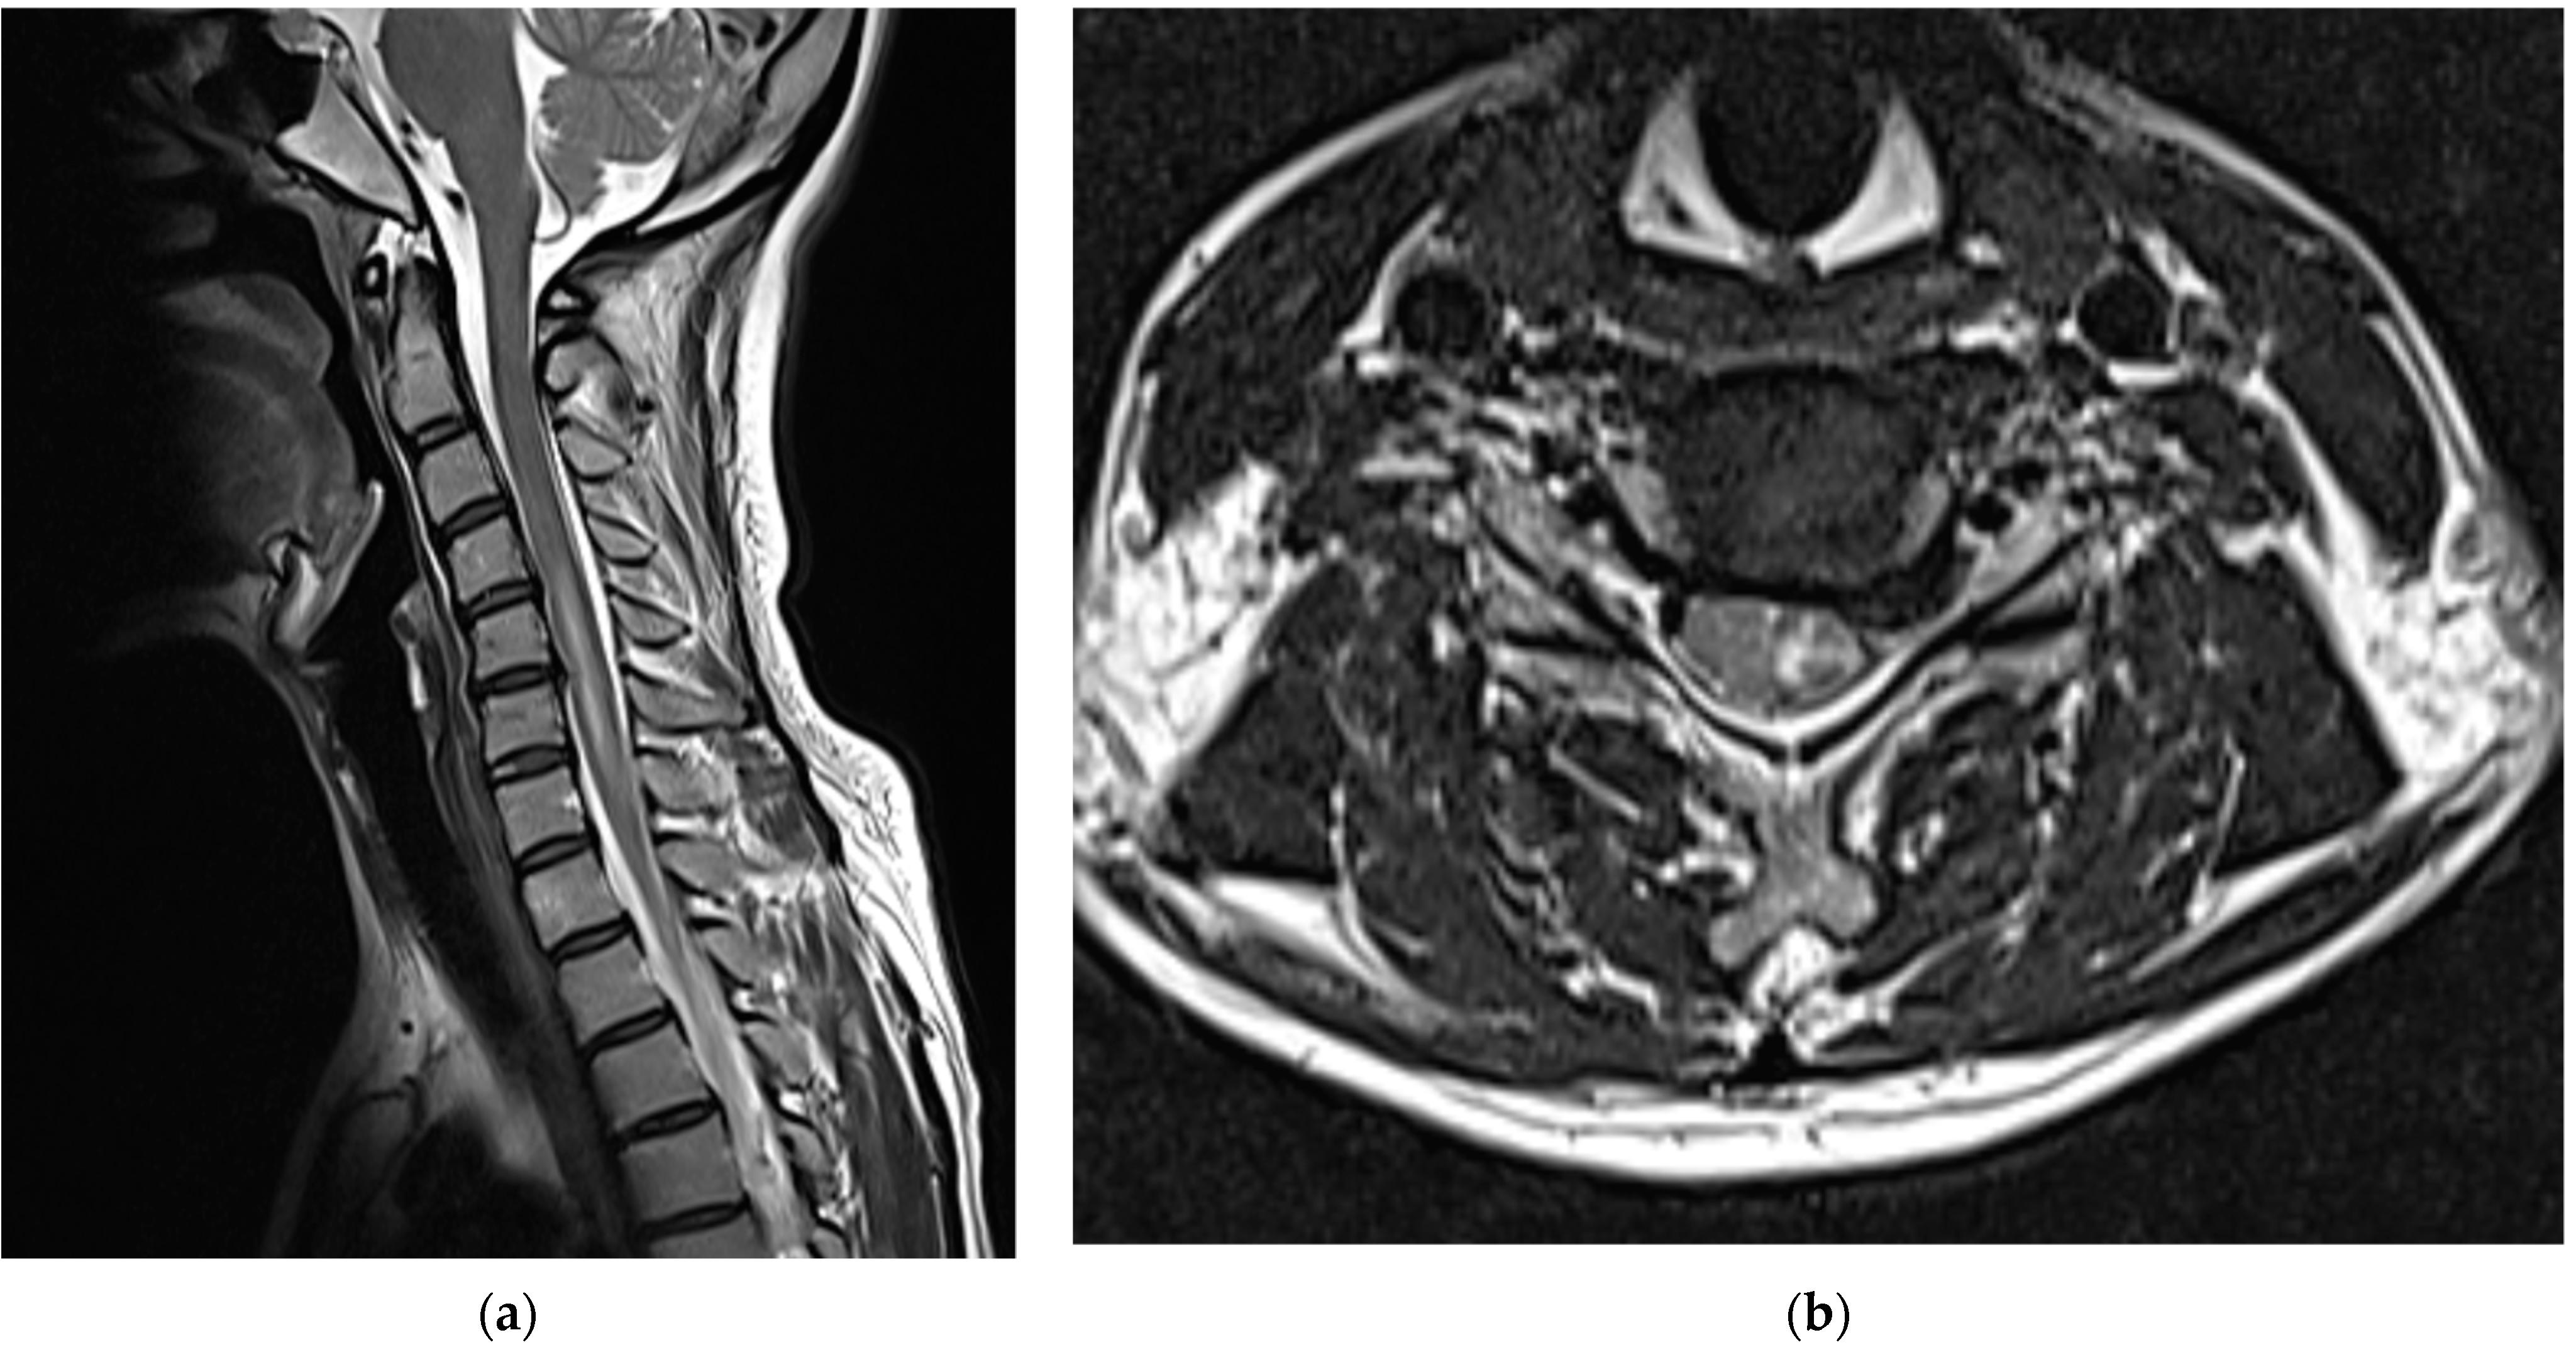

After consulting with neurosurgeons, no clear findings or symptoms of SDH other than PDPH were found; therefore, conservative treatment was provided. When the cervical spine MRI scans obtained on the second day of the procedure were compared with those obtained immediately before the procedure, intramedullary T2 high signal intensity and cord swelling from the C4/5 to C6/7 levels were observed, and the patient was diagnosed with a spinal cord injury (Figure 3).

Figure 3.

Cervical spine magnetic resonance images obtained on the second day of the procedure showed intramedullary T2 high signal intensity and cord swelling from C4/5 to C6/7 levels, which led to the diagnosis of a spinal cord injury: (a) T2-weighted sagittal images and (b) T2-weighted axial images of the C5/6 level.